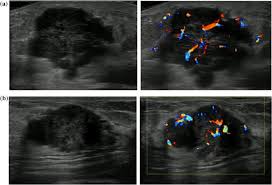

Ultrasound imaging allows better evaluation of the status of the axillary lymph nodes in patients with ibc, an important step in determining extent of disease prior to initiation of chemotherapy. However, a dark spot on your ultrasound doesn't mean that you. It is the most common cause of cancer death in women. in 2005 alone, 519 000 deaths were recorded due to breast cancer. this means that one in every 100 deaths worldwide and almost one in every 15 cancer deaths were due to breast cancer. On ultrasound, a breast cancer tumor is often seen as hypoechoic, has irregular borders, and may appear spiculated. In the table the differences in ultrasound appearances are listed.

Cysts, tumors, and growths will appear as dark areas on the scan. Breast ultrasound uses sound waves to make a computer picture of the inside of the breast. What does a solid mass look like in an ultrasound breast image? Ultrasound of triple negative breast cancer. This is a network of thin tubes (vessels) and nodes that carry a clear fluid called lymph around the body. A breast ultrasound is most often done to find out if a problem found by a mammogram or physical exam of the breast may be a cyst filled with fluid or a solid tumor. Solid lesions can be a little brighter or darker than the surrounding tissue, and the way to evaluate these on ultrasound is to look closely at the margins or the outer edges of the nodule. In the table the differences in ultrasound appearances are listed. Ibc is a rapidly progressive, aggressive form of breast cancer associated with a low overall survival rate. On the flip side, there are benign (not cancerous) breast changes which can mimic breast cancer as well. What does breast cancer look like on a mammogram? American cancer society, 9 oct 2017. Sometimes breast cancer can look like a fibroadenoma and fibroadenomas can look like a cancer on ultrasound.

Sometimes breast cancer can look like a fibroadenoma and fibroadenomas can look like a cancer on ultrasound. Ultrasound imaging allows better evaluation of the status of the axillary lymph nodes in patients with ibc, an important step in determining extent of disease prior to initiation of chemotherapy. Any area that does not look like normal tissue is a possible cause for concern. However, a dark spot on your ultrasound doesn't mean that you. If you're younger than 25.

This breast cancer ultrasound image shows changes related to breast cancer that are not seen as microcalcifications or a mass or lump. Any area that does not look like normal tissue is a possible cause for concern. If your breast tissue is too dense for a mammogram. Ultrasound imaging allows better evaluation of the status of the axillary lymph nodes in patients with ibc, an important step in determining extent of disease prior to initiation of chemotherapy. If a solid lump shows on the scan you might need to have. It is the most common cause of cancer death in women. in 2005 alone, 519 000 deaths were recorded due to breast cancer. this means that one in every 100 deaths worldwide and almost one in every 15 cancer deaths were due to breast cancer. With ultrasound, the radiologist will probably be trying to get a sense of the internal texture of the breast lesion and surrounding area. Physical examination and mammogram can be more accurate in some settings. If there are calcifications within the nodular dcis, one may be able to see these on ultrasound as white flecks. The images that a breast ultrasound produces are in black and white. A diagnostic mammogram is used to check for breast cancer when there is a sign or symptom of disease. A breast ultrasound is most often done to find out if a problem found by a mammogram or physical exam of the breast may be a cyst filled with fluid or a solid tumor. To look more closely at a.

Any area that does not look like normal tissue is a possible cause for concern. Below are images of dcis on breast ultrasound. Ultrasound is not used on its own as a screening test for breast cancer. Ultrasound (us) shows an irregular, hypoechoic (dark gray) spiculated mass (arrow), highly suspicious for cancer. This is because it may miss some early signs of cancer.